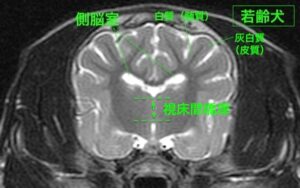

![[横断像(若齢犬)、T2強調画像]](https://saitovet.com/wp-content/uploads/2025/11/3-300x188.jpg)

右画像の若齢犬と比べてみると、

・脳のしわの部分(脳溝)が分かりやすい

・脳の外側と内側(灰白質と白質)の境目が分かりにくい

→脳の萎縮が疑われる

しかし本症例ではこれは異常ではなく、年齢的に正常な加齢性の脳萎縮であると判断できる。